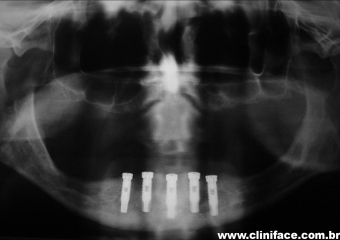

Raio X com prótese fixa instalada